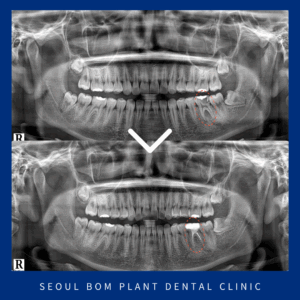

방이동치과 자연치아를 살리는 치료로

방이동치과 자연치아를 살리는 치료로 안녕하세요. 서울봄플란트치과 대표원장 송원섭입니다. 앞니는 눈에 잘 띄는 위치 있어 심미적으로 중요한 곳 중 하나인데요. 만약 이 부위가 갑작스럽게 깨지거나 부러지는 상황이…